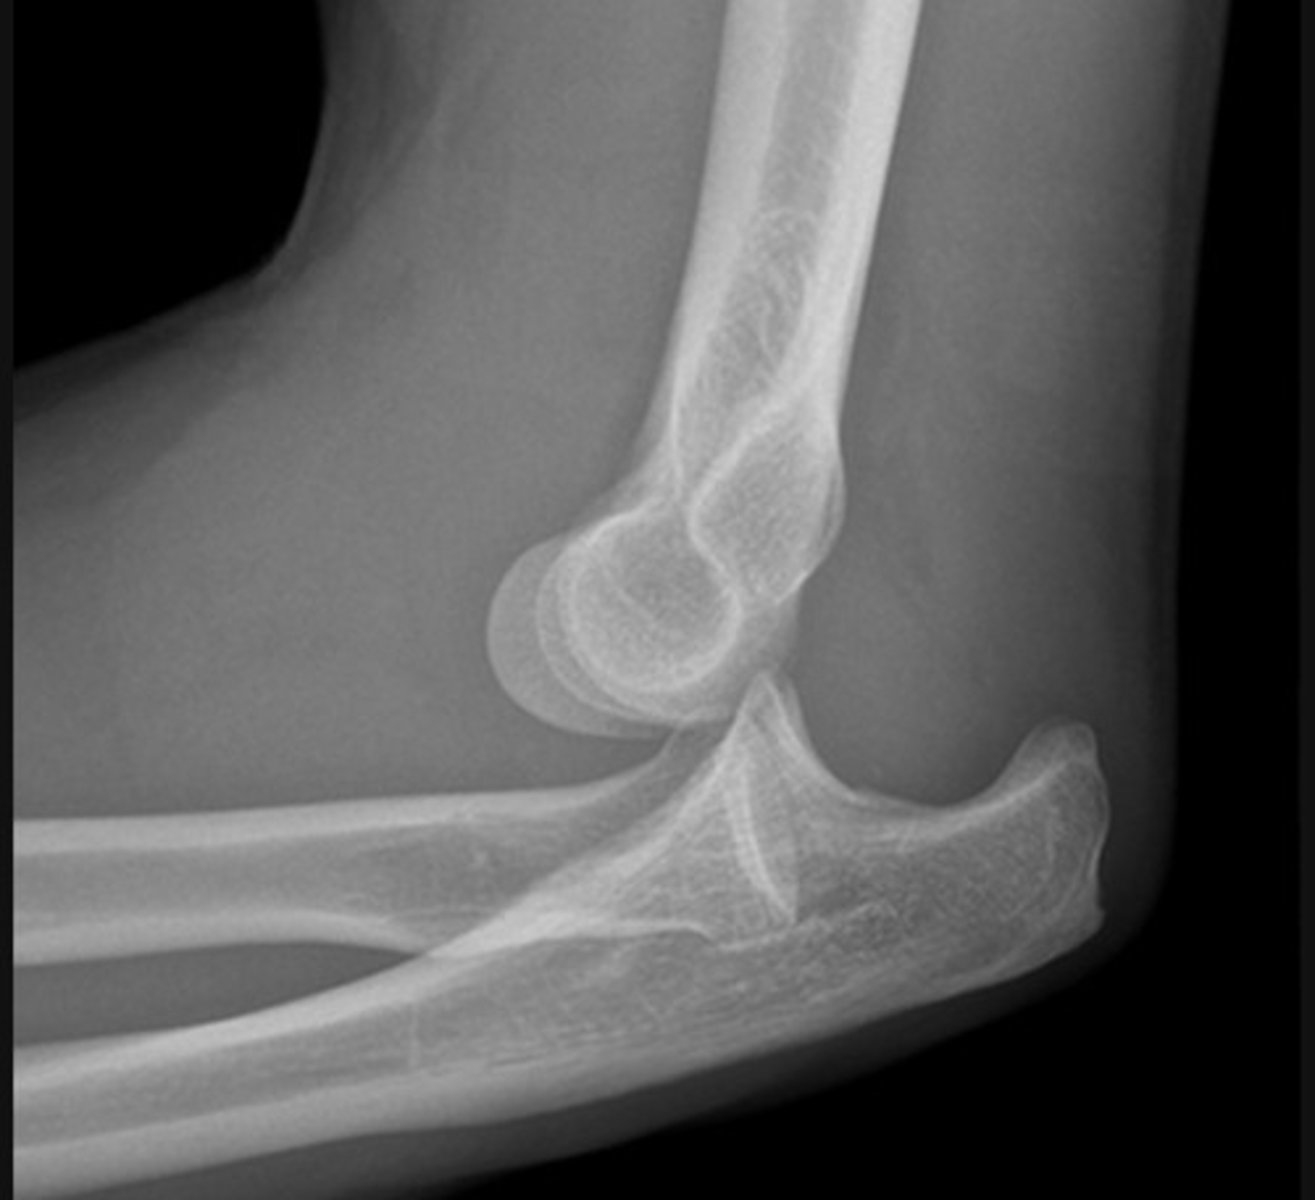

The ulna has dislocated posteriorly from the trochlea of the humerus

The radius has dislocated from the capitulum of the humerus

Visible posterior fat pad.

A joint effusion raises the anterior and posterior fat pads, indicating intra-capsular injury